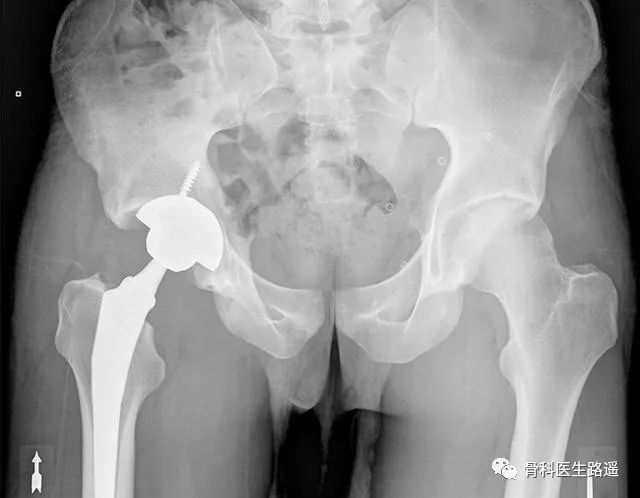

没办法,在他20岁那年,男孩不得不接受右侧全髋置换手术,把自己右边的股骨头和髋臼全部换成了人工假体(术后如下图)。